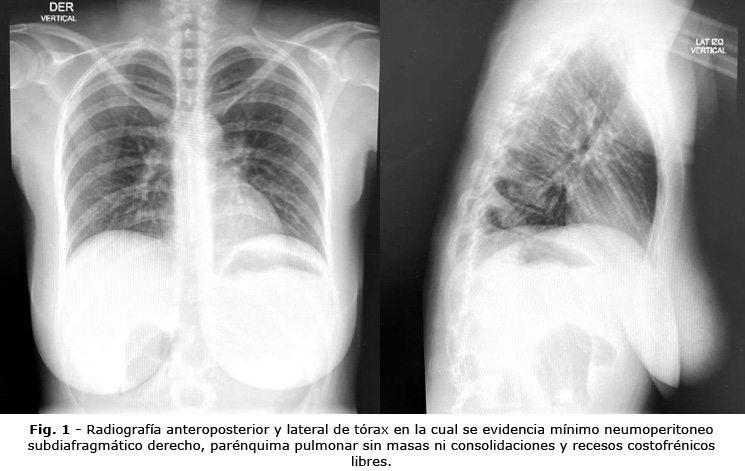

Ante la sospecha de posible perforación secundaria, se decidió solicitar radiografía toracoabdominal de pie, para evaluar la presencia de neumoperitoneo. Se realizó radiografía del tórax en la cual se evidenció neumoperitoneo subdiafragmático derecho reducido (Fig. 1). Se procedió a realizar tomografía axial computarizada (TAC) contrastada de abdomen, que reportó signos que sugerían perforación gástrica (engrosamiento de las paredes del estómago, asociado a neumatosis de la pared y aire libre intraperitoneal) (Fig. 2 y Fig. 3), asociados a cambios inflamatorios intraperitoneales.